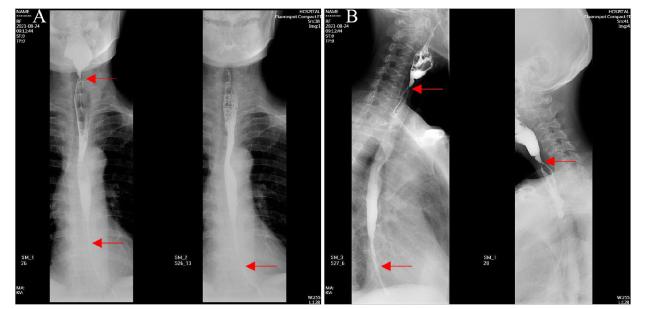

患者入院后于2021年8月24日行胃镜检查提示食管入口、食管中下段距门齿约30~40 cm处明显狭窄(图1A),予探条扩张后方能入镜至胃内,见胃窦变形,小弯侧大片溃疡形成,底覆白苔,周边黏膜充血水肿,幽门结构难以辨认(图1B),予球囊扩张(图1C),并放置鼻空肠管,术后第二天予肠内营养,但患者出现恶心、呕吐以及腹胀症状。2021年8月25日行上消化道碘剂造影显示食管上段、中下段狭窄,造影剂通过欠顺畅(图2);部分胃体、胃窦僵硬、狭窄并梗阻。心理科会诊提示患者有消极轻生念头,考虑为抑郁焦虑状态。经上述治疗后,患者肠内营养耐受情况欠佳,病情未见明显改善,梗阻仍然存在。经医务人员综合评估,确认该患者具有行PEG/J的适应证,无禁忌证。获得患方知情同意后,于2021年8月28日在气管插管全身麻醉下行PEG/J。患者取仰卧位,麻醉后经口插入胃镜,见食管仍狭窄,入镜至胃内,见胃腔变形,胃底较多胃液潴留,吸净后继续入镜至胃窦、幽门前区,见幽门仍狭窄,仔细辨认后送镜至十二指肠,见球部、降段黏膜光滑,退镜至胃体部,注气后于左上腹反复运用传统指压试验及透光试验寻找理想穿刺点,由于胃腔变形、胃移位,术者反复多次选点失败,后联合运用负压针吸试验,用含5 mL 生理盐水的注射器抽吸针筒保持负压,同时保证胃腔内充分注气,再次选定穿刺点后经腹部皮肤逐层缓慢穿刺至胃腔(图3A),最终定位于剑突下2 cm偏左约3 cm,消毒铺巾后,采用牵拉法完成胃造瘘术,并经胃造瘘管(管径6 mm)送入小肠管(管径3 mm)至空肠上段(图3B[5]。患者术中、术后生命体征平稳。于术后6 h开始向小肠管内注入少量营养液并逐量增加至正常管饲量,后逐渐过渡至日常食糜。经处理,患者病情及营养状况逐渐好转,于2021年9月25日出院。1个月后患者遵嘱返院复诊,监测体质量由住院期间最轻时39 kg增至47 kg,复查碘剂造影示食管上段狭窄较前减轻,中下段食管狭窄;胃窦部至幽门区明显狭窄伴梗阻,仅见少许造影剂通过幽门。医师与患方保持电话随访至撰稿日,得知患者呕吐次数逐渐减少至缓解,营养状况持续改善,造瘘管固定良好,造瘘口无红肿、渗液等(图3C)。

图1 一例上消化道严重腐蚀患者的胃镜图片

注:A 为食管入口;B 为胃窦及幽门处;C为 球囊扩张幽门入口。